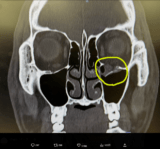

【フォト】骨がポッキリ!YA-MANのレントゲンと現在の顔 (写真はクリックで拡大します)

・【フォト】骨がポッキリ!YA-MANのレントゲンと現在の顔